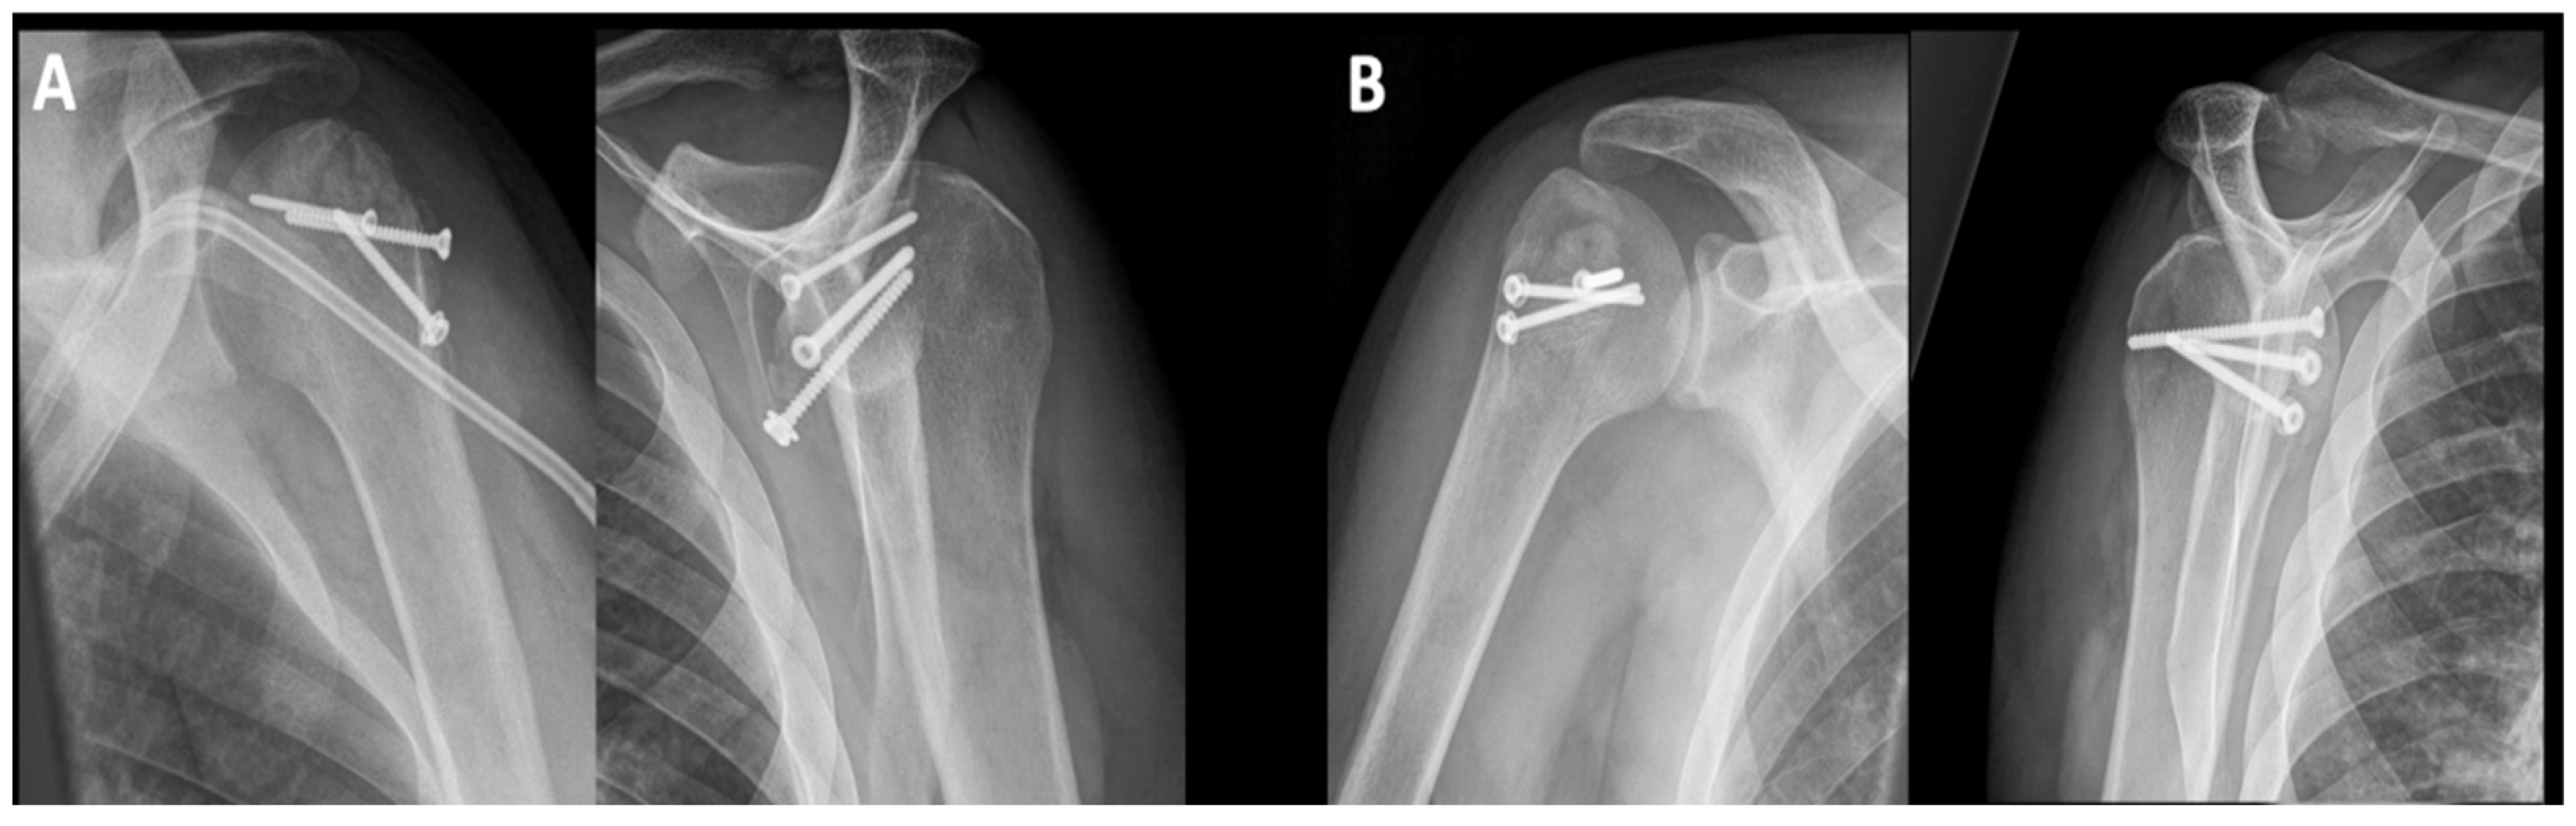

3.1. Impression Type Fractures (ITFs)

3.2. Surgical Neck Fractures of the Humerus (SNFs)

| 3 | 48 | M | ITF | SPO, 1x screw | 5.4 |

| 4 | 28 | M | ITF | Allograft, 6x screw | 2.4 |

| 5 | 33 | M | ITF | Allo- and autograft, 3x screw | 2.8 |

| 6 | 33 | M | ITF | Allo- and autograft, 3x screw | 2.8 |

| 7 | 27 | W | ITF | Allograft | 3.3 |

| 8 | 47 | M | ITF | Allograft | 3.4 |

| 9 | 47 | M | ITF | Mod. McLaughlin procedure, 3x screw | 4.6 |

| 10 | 29 | M | ITF | Autograft, 2x screw | 4.6 |

| 11 | 45 | M | ITF | Allo- and autograft, 3x screw | 4.3 |

| 12 | 35 | M | ITF | Autograft, 2x screw | 8.4 |

| 13 | 39 | M | SNF | DPO | 5.9 |

| 14 | 48 | W | SNF | DPO | 2.7 |

| 15 | 68 | M | SNF | Allo- and autograft, 2x screw, SPO | 2.2 |

| 16 | 47 | M | SNF | 2x screw, SPO | 2.3 |

| 17 | 45 | M | SNF | Autograft, 2x screw | 4.2 |

| 18 | 60 | W | SNF | SPO, 2x screw | 2.5 |

| 19 | 58 | M | SNF | Autograft, SPO, 1x screw | 2.1 |